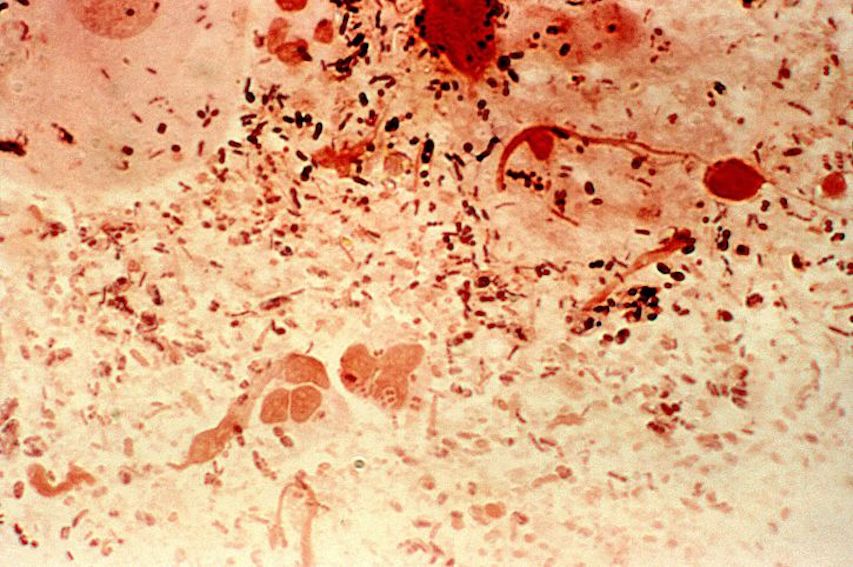

Gonorrhoea infection causing by bacteria Neisseria gonorrhoeae in male Gonorrhea Untreated If cervicitis goes undetected and untreated, ascending gonococcal infection can result in upper reproductive tract involvement, such as salpingitis and pelvic. Untreated gonorrhea may also increase your chances of getting or giving hiv. This is a potentially serious infection of the female reproductive tract. If you believe you have gonorrhea, don’t wait to seek treatment. Gonorrhea is a sexually transmitted. Gonorrhea Untreated.